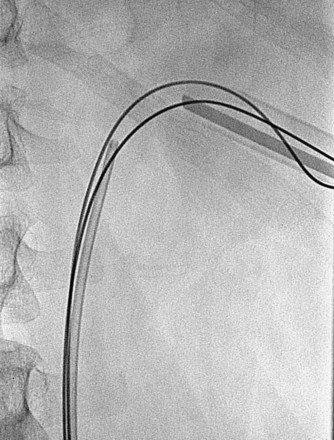

The “ultimate” retrograde assistance to percutaneous access into the upper urinary tract collecting system is the retrograde approach to percutaneous access. Although the antegrade approach is much more commonly performed, a retrograde approach may be selected when the surgeon has limited experience with antegrade percutaneous renal puncture or in situations in which there might be a technical advantage to the retrograde approach such as morbid obesity or a hypermobile or abnormally situated kidney (Mokulis and Peretsman, 1997). The Lawson Retrograde Nephrostomy Wire Puncture Set (Cook Urological; Spencer, IN) is the device commercially available for this use. After retrograde placement of a guidewire into the renal pelvis, pass the 7-Fr Torcon catheter—which is actively deflectable from 0 to 140 degrees (Fig. 47–14A)—over the guidewire and into the desired calyx. Insert the 3-Fr polytetrafluoroethylene (PTFE) sheath containing the 0.017-inch stainless steel puncture wire through the Torcon catheter. Advance the puncture wire through the kidney and body wall under fluoroscopic control, withdrawing and repositioning it if any obstacles such as a rib are encountered (Fig. 47–14B). Make a small skin incision and grasp the wire externally. Use the fascial dilators in an antegrade fashion until the Torcon catheter can be advanced through the tract. Once the end of the catheter exits the skin, exchange the puncture wire for a standard 0.035 inch guidewire, thus attaining through-and-through access.